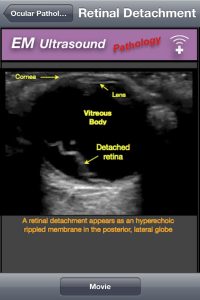

Ahora pasamos a la sección de escaneos, donde tenemos tambien, sus indicaciones, así como la tecnica para realizar el estudio, la anatomía normal, y las distintas patología que podemos diagnosticar usando la ultrasonografía.

Lo único que no me agrado de la aplicación es que, en lugar de tener su contenido en texto, son imágenes de no muy buena calidad, en cuanto al texto me refiero, ya que las imagenes de los ultrasonidos están muy entendibles y con sus respectivas anotaciones.